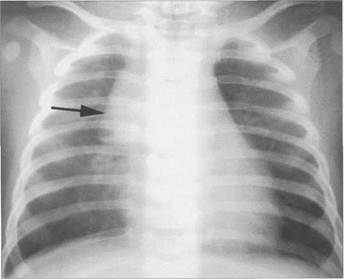

Рис. 9.8. Рентгенограмма грудной клетки в прямой проекции ребенка 2 месяцев.

1 — наружный контур сердца; 2 — наружный контур вилочковой железы; 3 — поперечник грудного позвонка; 4 — поперечник вилочко­вой железы не превышает двух поперечников грудного позвонка.

В возрасте до 1 года железа считается нормальной, если ее поперечный размер на уровне бифуркации трахеи не превыша­ет двух поперечников грудного позвонка (рис. 9.8).

При нормальных размерах наружный контур вилочковой железы не должен выходить за пределы медиальной трети соответствующей половины грудной клетки, а нижняя граница должна находиться в пределах ее верхней трети. Рентгенограмма в прямой передней проекции. Конфигурация вилочковой железы на обзорной рентгенограмме непостоянна и зависит от ее величины, фазы дыхания, величины сердца, кро­венаполнения сосудов. Наружный контур железы чаще бывает выпуклым в виде одиночной дуги, но может быть вогнутым, выпрямленным, волнистым. Идентифицировать вилочковую железу можно по перечисленным ниже признакам.